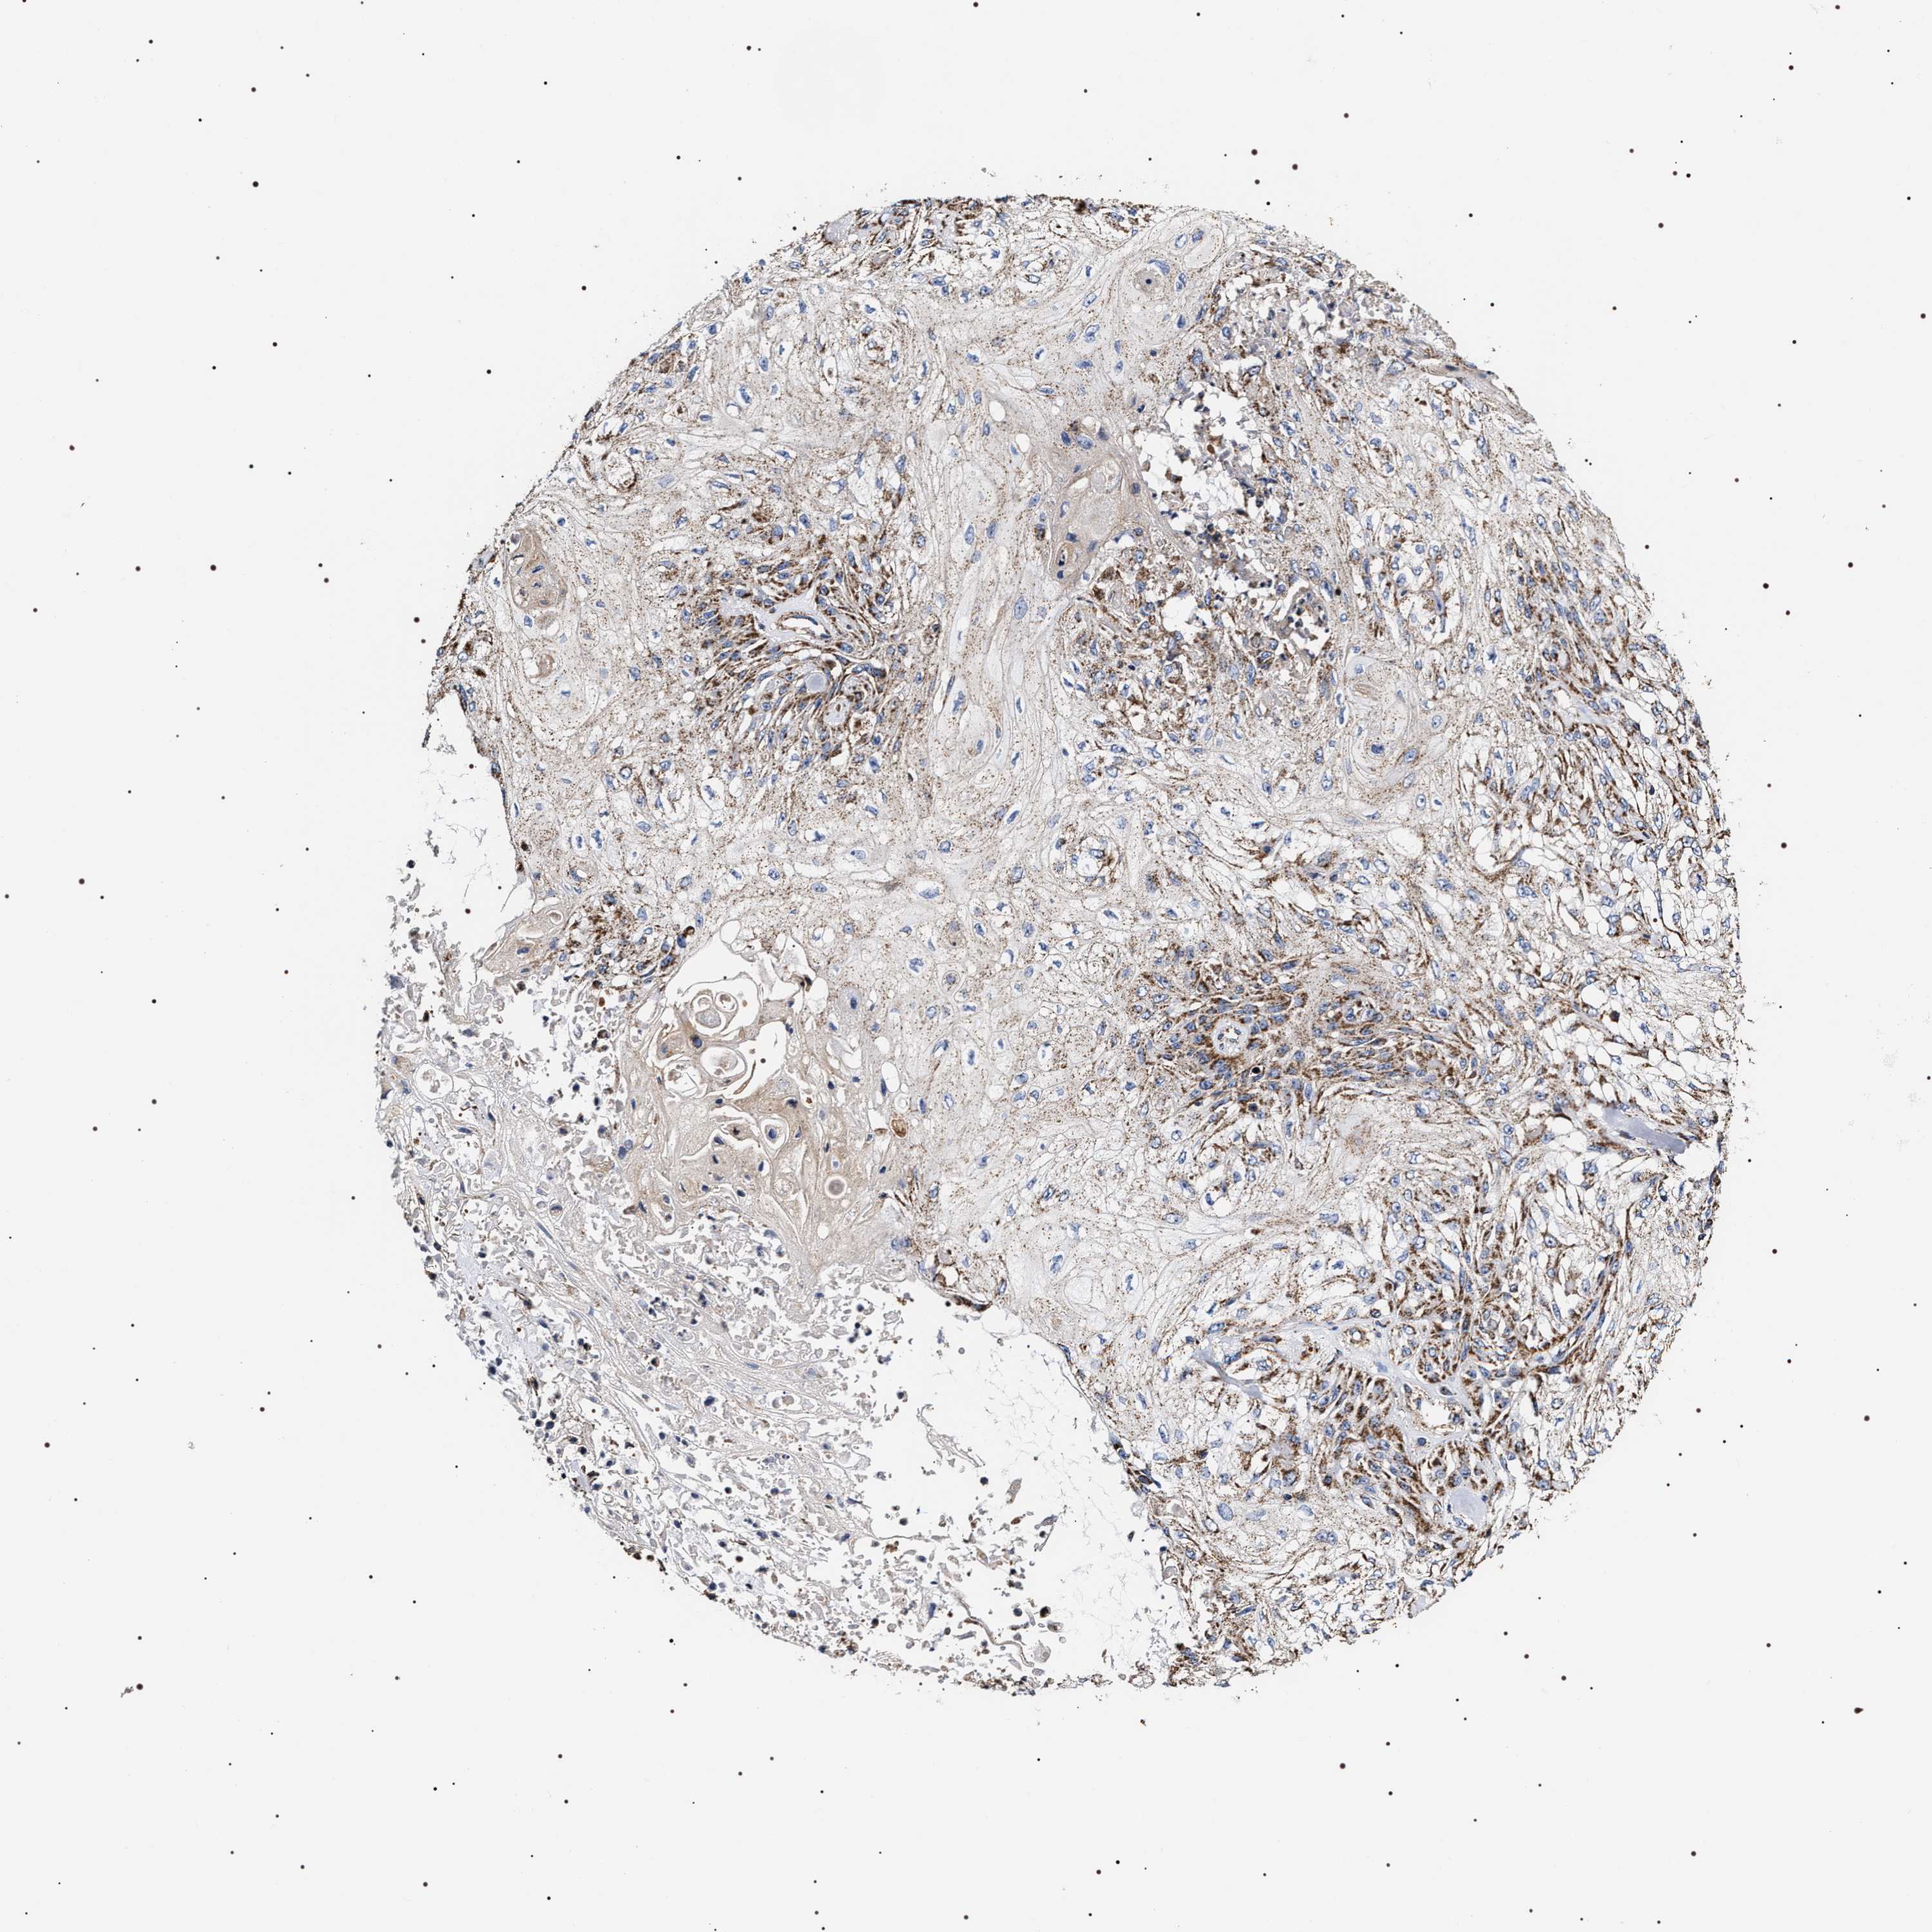

Basal cell and squamous cell cancer

SKIN CANCER - Protein expressioni

A mouse-over function shows sample information and annotation data. Click on an image to view it in a full screen mode. Samples can be filtered based on level of antibody staining by selecting one or several of the following categories: high, medium, low and not detected. The assay and annotation is described here.

Each image is clickable and will lead to virtual microscopy that enables deeper exploration of all samples and also displays staining intensity scores, fraction scores and subcellular localization as well as patient and tissue information for each sample.

Antibody HPA020300

Staining

High

Medium

Low

Not detected

Intensity

Strong

Moderate

Weak

Negative

Quantity

>75%

75%-25%

<25%

None

Location

Nuclear

Cytoplasmic/membranous

Cytoplasmic/membranous,nuclear

Basal cell carcinoma